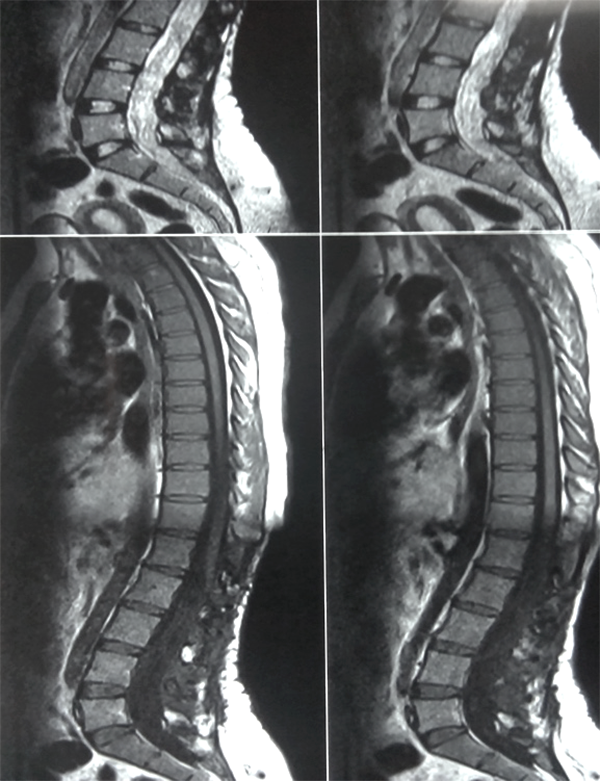

Figura 5: Caso 1. Astrocitoma Pilocítico cervical. A: preoperatoria. B: Cifosis 2 años post resección. Marcada “atrofia” medular.

Es evidente que el límite entre el tejido medular y tumoral en las lesiones como los astrocitomas es indiscernible lo que dificulta la posibilidad de resección completa; en los tumores como los ependimomas esta diferencia es más franca y permite seguir un plano de disección seguro (Figuras 3, 4 y 5). Lo anterior condiciona nuestros resultados como han puntualizado diversos autores.5,8 El estado general previo a la cirugía requiere de una valoración juiciosa de las posibilidades de resección. Por ejemplo, el caso 12 (Figura 6) es una paciente portadora de Enfermedad de Von Hippel Lindau, Hemangioblastoma cervical biopsiado en otra institución del exterior del país, fijación de columna cervical y sindrome de Cushing por exceso de medicación corticoidea cuya cirugía debió suspenderse en dos oportunidades por la disminución de su capacidad ventilatoria. Con estos antecedentes y la delgada capa de tejido medular evidenciada intraoperatoriamente se optó por una resección subtotal. A los cuatro meses de la cirugía la paciente recuperó la marcha autónoma y demás parámetros clínicos.